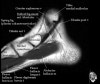

발목 관절의 MRI 단면 영상

- Sagittal section

Bones and marrow

Joint fluid

Talar dome

Subtalar joints

Achille's tendon

Sinus tarsi

Plantar fascia